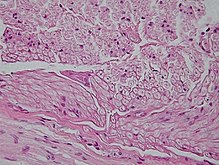

Die einzelnen Axone eines Nervs sind von einer bindegewebigen Hülle umschlossen, die als Endoneurium bezeichnet wird. Mehrere Axone sind zu Nervenfaserbündeln, sogenannten Faszikeln, zusammengefasst, die wiederum von Bindegewebe (Perineurium) umhüllt sind. Die Bindegewebshülle um den gesamten Nerv wird als Epineurium bezeichnet.